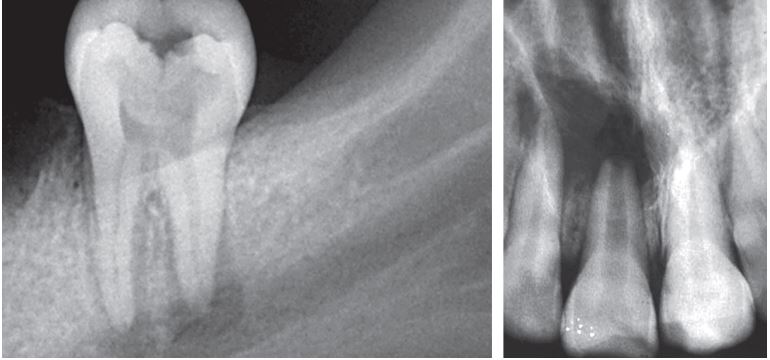

– Đẩy chất bẩn quá chóp (H21.4).

- Vật liệu trám bít ống tủy quá chóp (H21.6).